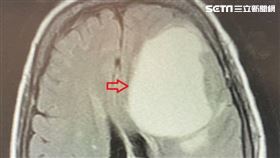

62歲張先生年初自費接受高階健檢,腦部電腦斷層血管造...

2020/07/08 07:43